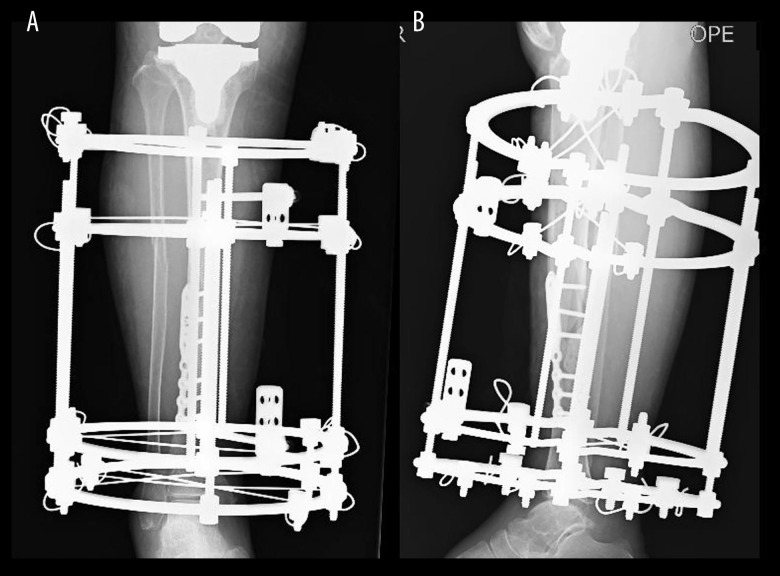

BACKGROUND Periprosthetic tibial fractures following total knee arthroplasty (TKA) are increasingly encountered in very elderly patients, where multiple comorbidities and osteoporosis compromise early mobilization and elevate the risk of complications. Maintaining pre-injury activities of daily living (ADL) while ensuring safe surgical management is challenging. We present a case of a 95-year-old woman with a periprosthetic tibial shaft fracture managed with open reduction, additional plate fixation, and Ilizarov external fixation, enabling immediate postoperative weight-bearing. CASE REPORT A 95-year-old woman who sustained a periprosthetic tibial shaft fracture after a fall had been independently ambulatory indoors and used a cane outdoors. On admission, radiographs showed a Felix Type III tibial fracture. Six days after the injury, the fracture was stabilized using Ilizarov external fixator with additional internal fixation using a small locking plate. This combined approach allowed immediate full weight-bearing from the day after surgery. She had no major complications; a minor pin-site infection was managed conservatively. Bone union was confirmed on computed tomography (CT) at 4 months, and the external fixator was removed. At 1 year, radiographs showed good alignment, and she walked independently without a cane. CONCLUSIONS This case demonstrates that combining Ilizarov external fixation with internal plate fixation can enable immediate postoperative weight-bearing and functional recovery, even in very elderly patients with periprosthetic tibial shaft fractures and severe osteoporosis.

背景:全膝关节置换术(TKA)后胫骨假体周围骨折越来越多地出现在高龄患者中,其中多种合并症和骨质疏松症损害了早期活动并增加了并发症的风险。维持损伤前的日常生活活动(ADL),同时确保安全的手术管理是具有挑战性的。我们报告了一例95岁的女性假体周围胫骨干骨折,采用切开复位、附加钢板固定和Ilizarov外固定,使术后立即负重。病例报告:一名95岁的女性在跌倒后发生假体周围胫骨轴骨折,在室内可以独立活动,在室外使用拐杖。入院时,x线片显示Felix III型胫骨骨折。受伤6天后,使用Ilizarov外固定架稳定骨折,并使用小锁定钢板进行额外内固定。这种联合方法可以在手术后的第二天立即完全负重。她没有重大并发症;轻微的针部感染保守处理。4个月时,计算机断层扫描(CT)证实骨愈合,并拆除外固定架。1岁时,x光片显示对齐良好,无需拐杖即可独立行走。结论:本病例表明,Ilizarov外固定联合钢板内固定可以使术后立即负重和功能恢复,即使是非常高龄的胫骨干周围骨折和严重骨质疏松症患者。